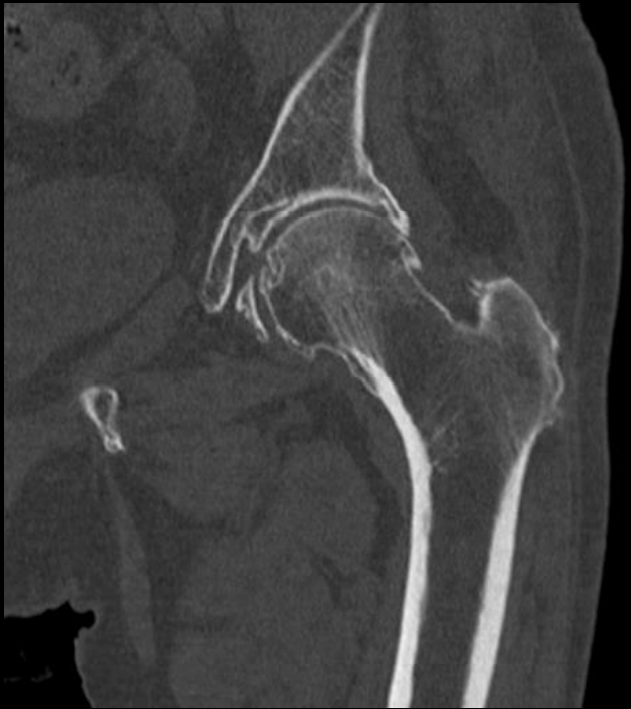

A tomografia computadorizada articular é um exame de diagnóstico por imagem de alta qualidade que, como o próprio nome indica, é realizado para analisar as articulações. No corpo humano, as articulações fazem parte do sistema articular e são responsáveis pelos diversos movimentos que realizamos. Uma articulação conecta ossos a outros ossos e cartilagens. São exemplos de articulações: joelho, ombro, cotovelo, punho, tornozelo, coxofemoral, temporomandibular, entre outros.